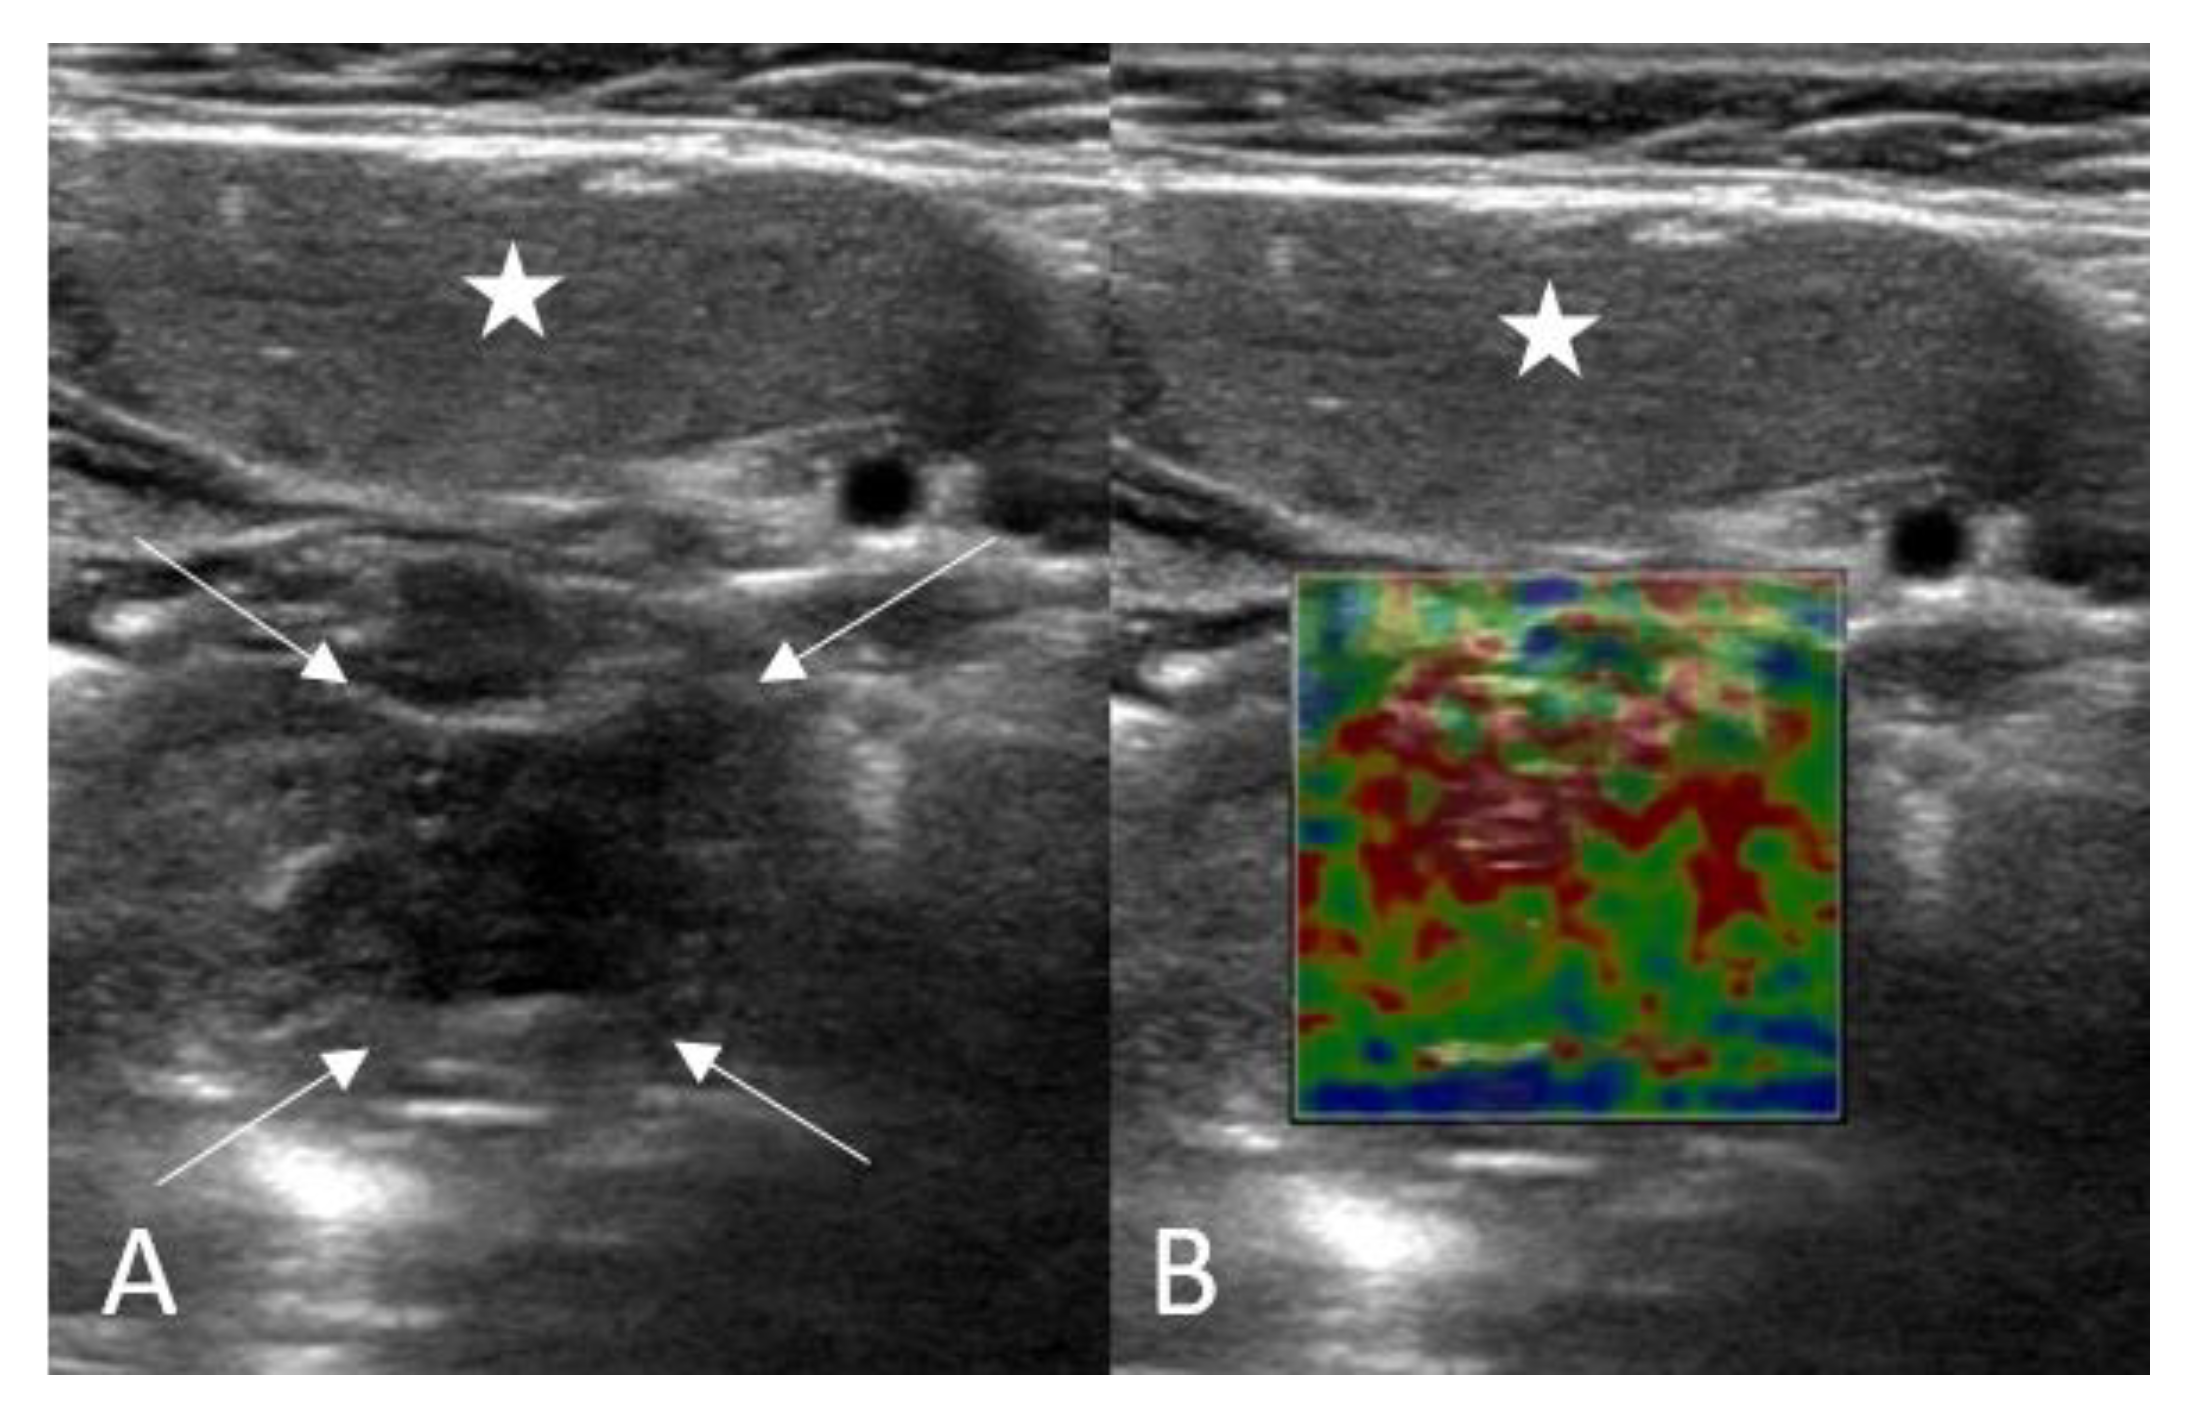

The volume of tonsils was automatically calculated using the US machine utilizing three simple measurements. Tonsil elastography measurements were determined automatically by the SWE feature of the machine (Figure 2). It was important to avoid applying pressure to the probe and to keep the practitioner’s hand stable throughout ultrasonographic imaging. Elasticity values were measured in kilopascals (kPa). Elasticity values of the lesions were measured three times using three different ROIs of 1 cm2 from the different areas by the same observer, and the average of these measurements was recorded as the final data. The US and SWE examinations were conducted by a radiologist with ten years of experience.

Figure 2.

Shear wave elastography (SWE) evaluation of the palatine tonsil (A,B): Asterisk: Submandibular gland, Arrows: Palatine tonsil).